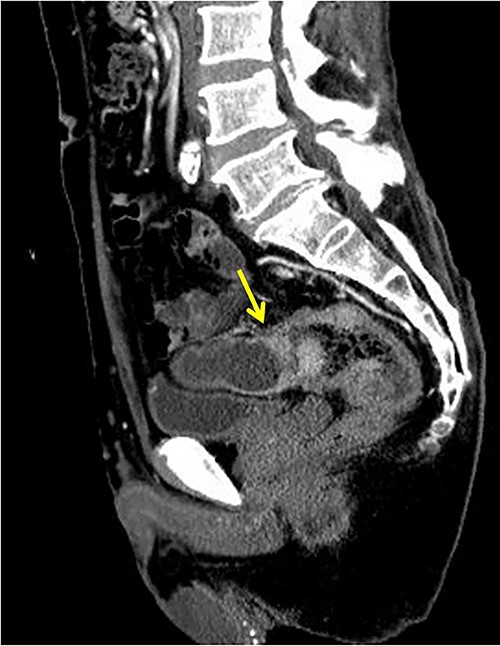

The patient was a 65-year-old man presenting to our hospital with complications of diarrhea for a year and weight loss. Colonoscopy showed rectal cancer on the anal verge (13 cm) with circumferential stenosis. Laboratory findings showed that the serum carcinoembryonic antigen (CEA) level was 4.7 μg/ml and that the serum carbohydrate antigen 19-9 (CA19-9) was 72.2 U/ml. A computed tomography (CT) scan of the abdomen showed thickening of the rectal wall with inflammation. Fistula formation between the ileum and the rectum was observed. Enlarged lymph nodes were also noted around the rectum and no enlarged mesenteric lymph nodes (Fig. 1). The patient was diagnosed with rectal cancer with ileum invasion and then scheduled to undergo surgery. We performed single-incision laparoscopic low anterior resection of the rectum with D3 dissection and partial resection of the ileum. Lymph node dissection, including the area of the inflow vessel, was also performed due to observed lymph node swelling in the mesentery of the ileum around the fistula formation intraoperatively. The operative time was 326 min, and the blood loss volume was 15 ml. Histopathological analysis revealed that the lymph nodes in the small intestine were positive for metastasis, and the diagnosis was pT4b (small intestine) N1 (2/16 (#251, 1/12, #252 1/4, #253 0/0)) M1 (small intestine mesenteric lymph node (1/1)), nonsolid type (por2) adenocarcinoma, ly3, v2 f Stage IV [TNM (tumor, nodes, metastasis) classification] (Fig. 2a and b). After discharge from the hospital, capecitabine plus oxaliplatin was administered for 6 months as adjuvant chemotherapy. The patient has been recurrence-free for 2 years after surgery.

Fistula formation between the small intestine and the rectum was observed. Enlarged lymph nodes were also noted around the rectum.

(a, b) Rectal cancer with small intestine invasion and fistula formation.